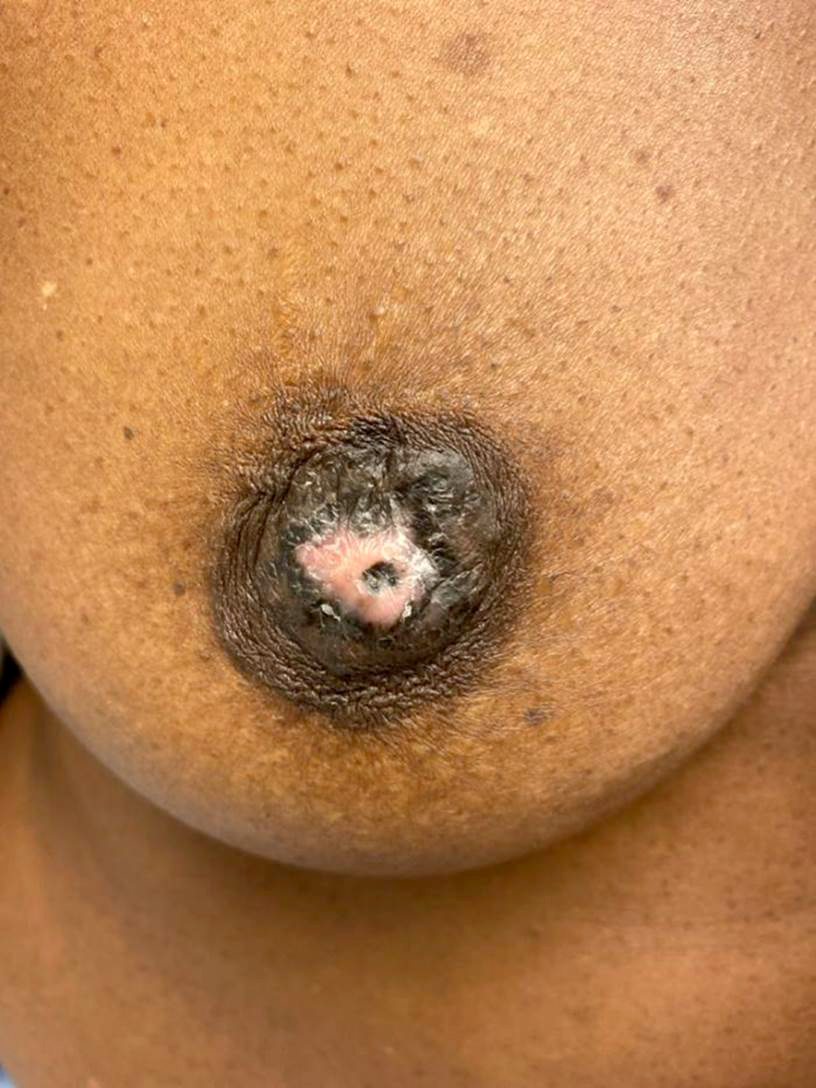

Clinical images

- Nipple areolar complex with red-pink crusting lesion, discoloration, thickening, ulceration, exudate, nipple retraction, etc.

- Typically well demarcated; epidermal involvement usually does not extend beyond the grossly evident lesion (Cancer Treat Rev 2001;27:9)

- Scaling crust may be removed by skin preparation prior to surgery